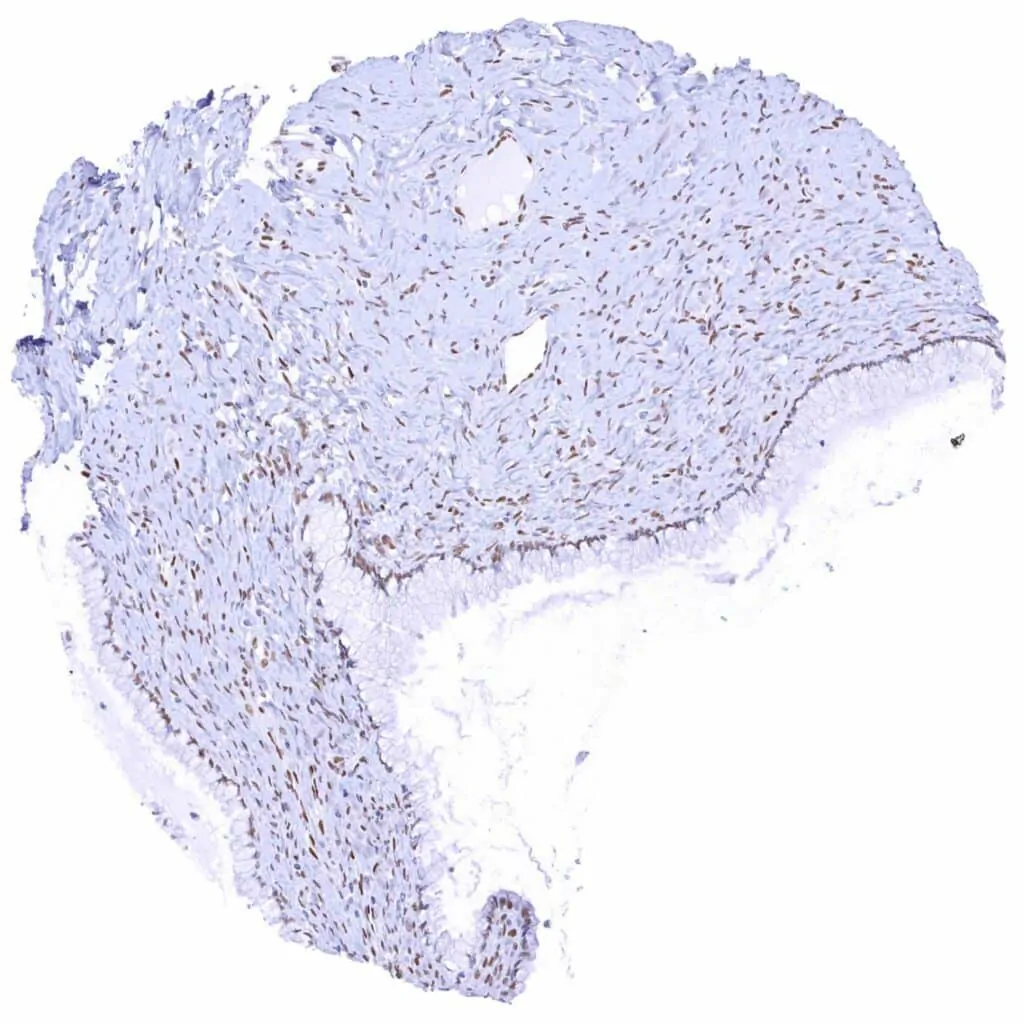

Uterus, myometrium – Weak to moderate TLE1 positivity of smooth muscle cells